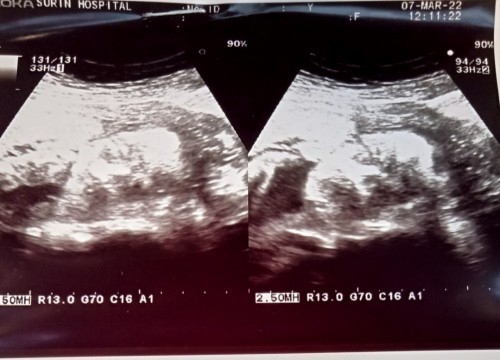

กำหนด29 มิถุนายน65ค่ะ

Post reply image